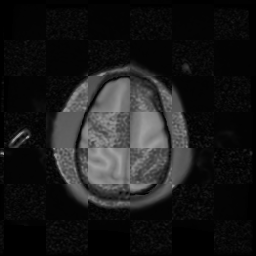

For each of the 10 subjects, we show checkerboard slices in each direction (1) before registration, first row; (2) after rigid->scaleversor->affine registration, second row; and (3) after BSpline registration, third row.

Gucci